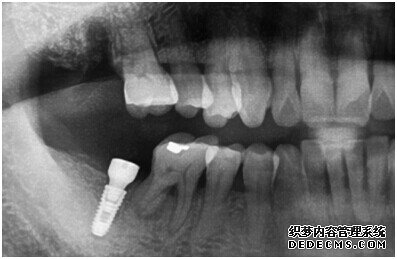

成功植入种植体后的效果图

种植体成功植入后的CT效果图

整个种植牙完成后的效果图